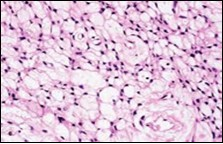

Figure 4.Soft tissue perineurioma composed of whorls and perivascular aggregates of neural cells with bipolar cytoplasmic processes, wavy, slender nuclei and commingled collagen fibres 13.